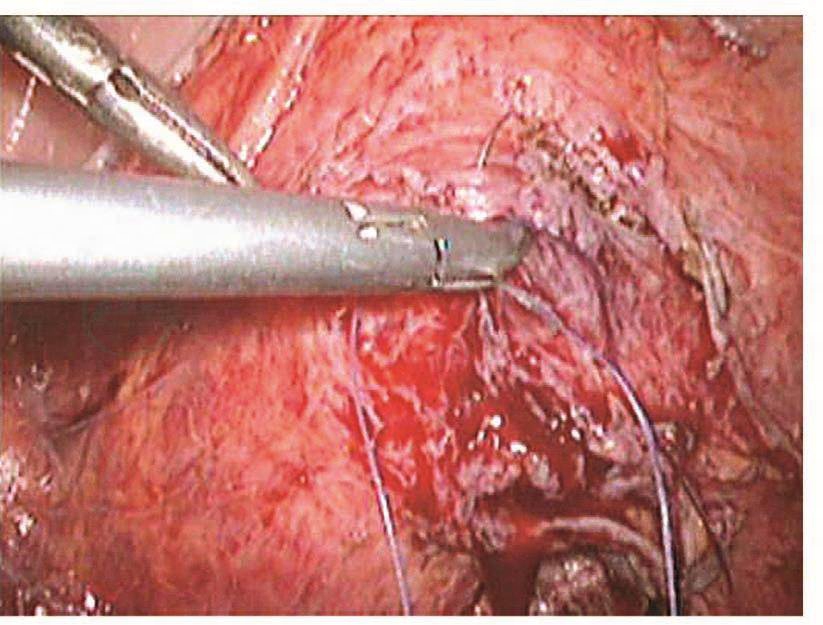

如果损伤长度>5mm,则需要手术处理。以往是先行暂时性肾盂造瘘下修补:根据笔者经验,如果术后15天内发现损伤,则可以直接采用腹腔镜下修补,可以减轻患者痛苦,缩短住院时间。该方法最关键的步骤是游离粘连的输尿管,因为,术后15天内组织开始出现明显的组织粘连。术前必须与患者及家属沟通并征得泌尿外科大夫同意后才进行手术。操作时,腹腔镜下探查盆腔,明确粘连程度及输尿管走向,分离粘连组织,暴露损伤的输尿管创面,从膀胱镜下插入导管,对合损伤面,用4-0的可吸收线在输尿管前、左、右三个方位各穿合一针。缝合时缝针从损伤口远端输尿管浆肌层进针,穿过黏膜层,再从近端黏膜层进针,穿出浆肌层,拉紧穿线,镜下打结。修补损伤面后,在膀胱镜下取出导管,再插入输尿管镜,明确输尿管通畅。然后,通过输尿管镜放进双J型支架,床边X线机明确双J管的位置,盆腔放置引流管,如果引流不多,48小时后取出。术后3个月在膀胱镜下取出双J管(图111~图116)。

图111 明确输尿管损伤部位

图112 游离输尿管

图113 将导管送进输尿管

图114 吻合输尿管

图115 修复后的输尿管

图116 放置引流管